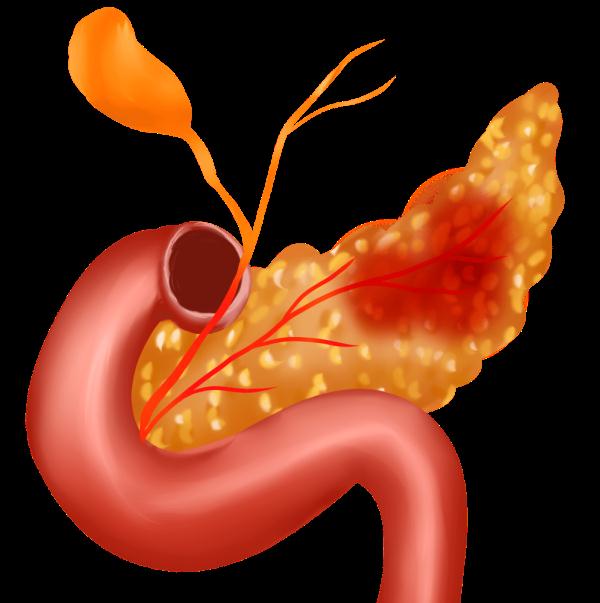

由于胆管和胰管共同开口于十二指肠降部的主乳头部,如此处梗阻,不仅可导致胆汁返流入胰管,还可导致壶腹部功能障碍,导致肠液返流入胰管。因胆汁为碱性,胰液中的消化酶在碱性环境下容易被激活,导致多种胰酶的酶原在胰腺导管和腺泡内被提前激活,产生胰腺的自我消化,从而导致胰腺自身消化的化学性炎症,导致急性胰腺炎。

胰腺为什么会自己"消化"自己?

以胆源性胰腺炎为例,胆囊结石或胆管结石,在胆道移行的过程,引起胆管梗阻,胆汁淤积,不仅可引起梗阻性黄疸和急性胆管炎,如结石堵塞胆胰管结合部,即胆胰管共周开口的十二指肠主乳头的壶腹部,导致壶腹部功能障碍,胆汁或十二指肠液返流入胰管,由于胆汁是碱性、肠液中含有肠激酶等可激活胰液中的胰蛋白酶原,导致胰蛋白酶在胰腺中提前激活,胰蛋白酶除可自身激活外,还可激活糜蛋白酶等多种消化酶,导致胰腺腺泡中的胰原颗粒中的各种酶原被提前激活,此为酶原在胰腺腺泡中激活的级联反应,多种消化酶在胰腺腺泡内激活后,会自身消化胰腺组织,就是所说一发狠可是会把自己"吃掉"的!

自身消化的过程中,多种炎症细胞就会聚集到炎症反应处,释放多种细胞因子和炎症介质,这些细胞因子和炎症介质又可自身崔化,导致炎症风暴的发生,从而导致急性重症胰腺炎的发生。